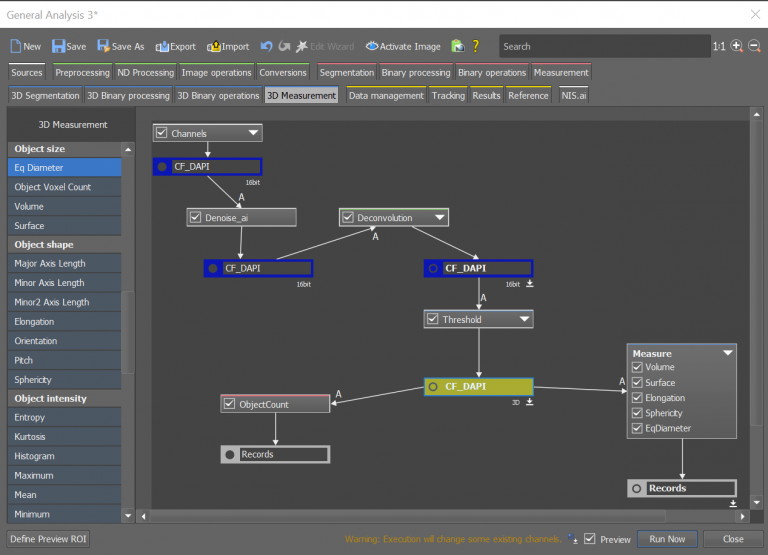

Morphological studies of the acinar structures were accomplished using NIS-Elements General Analysis (GA3), an analysis pipeline with artificial intelligence (AI) capabilities. The combination of multiple conventional segmentation tools and AI techniques can enable customized measurements tailored to specific experiments, and this can be employed across high-content datasets as well. As represented in Figure 7A, we created an analysis pipeline based on five steps: Denoising, Deconvolution, Thresholding, Object counting and Measurements. The previously acquired high-content data can be automatically analyzed using this procedure, obtaining information about volume (um3), surface (um2), elongation (um), sphericity and diameter (um), allowing us to gain more insight into the morphological characteristics of 3D breast cultures (Figure 7B).

A

B

Figure 7: Automated high-content data analysis for morphological profiling of 3D breast culture acini. Analysis pipeline built via GA3 analysis (A) to obtain information on the volume, surface area, elongation, sphericity, and diameter of 3D breast spheroids (B).

The images were acquired by using JOBS module of NIS-Elements Microscope Imaging software (Nikon) (Figure 3). Morphological studies of the acinar structures were accomplished using NIS-Elements GA3 (Nikon) (Figure 7).